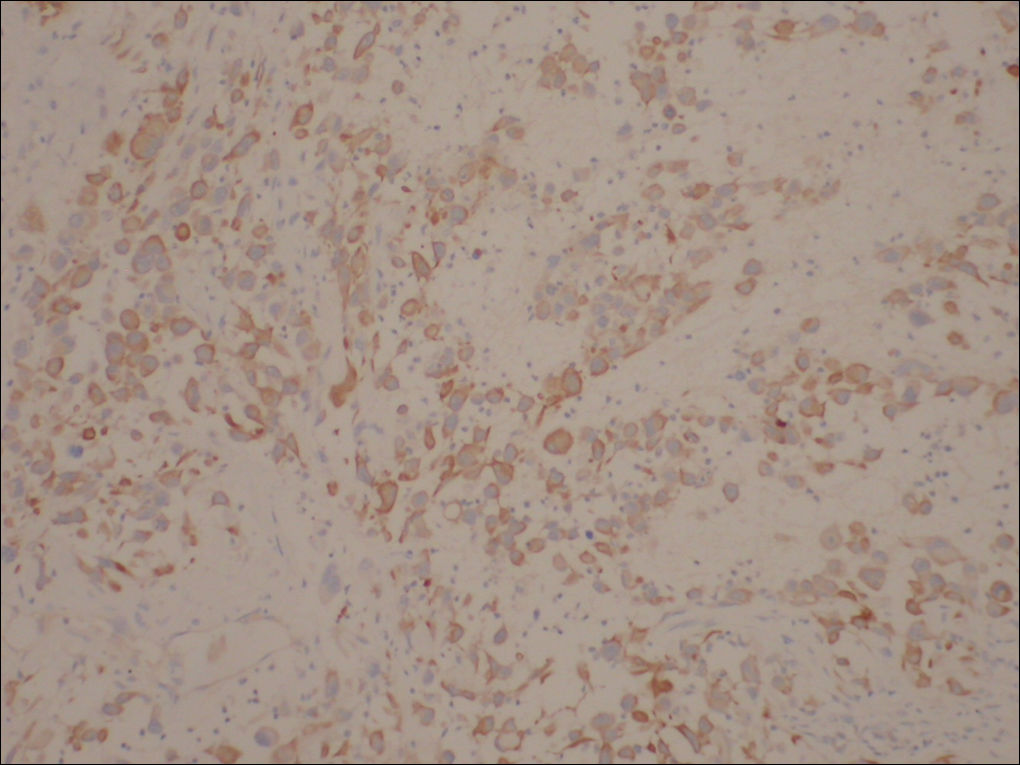

免疫组化结果:

阳性:  CKVimCK5/6CK14

阴性:  MyoD1MyogeninDesminSMAEMACD34HMB45CK8/18CEA

特染:  AB-PAS(-)